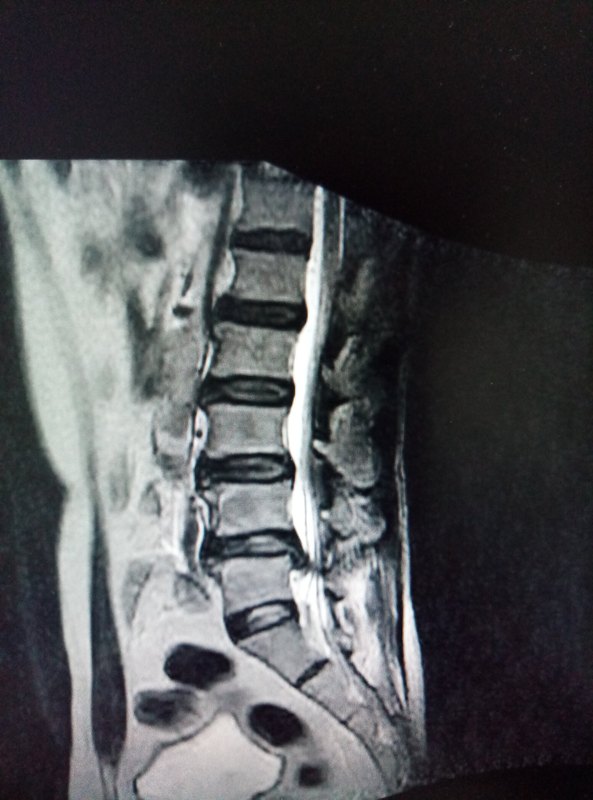

- 精選 腰椎間盤的微創(chuàng)治療

患者腰痛伴右下肢麻痛不適,難以入睡,在外行各種治療,均無效,到我處就診,腰部壓痛,右下肢小腿外側(cè)麻木,術(shù)前檢查在我處給予微創(chuàng)治療后患者癥狀完全緩解術(shù)后4月行檢查示 術(shù)后8個(gè)月復(fù)查微創(chuàng)治療能完全根治腰椎間盤突出 手術(shù)創(chuàng)傷小